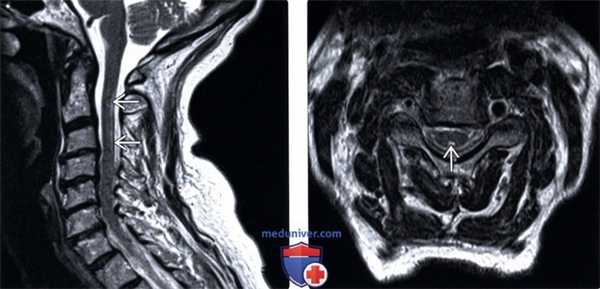

(Слева) Сагиттальный срез, Т2-ВИ: нечетко ограниченная гиперинтенсивность Т2-сигнала и минимальное увеличение объема шейного отдела спинного мозга. Патологические изменения Т2-сигнала дорзальных столбов спинного мозга обычно имеют протяженность в несколько тел позвонков.

(Справа) Аксиальный срез, Т2-ВИ: гиперинтенсивность Т2-сигнала в виде характерной «перевернутой буквы V» в области задних столбов спинного мозга, что с высокой долей вероятности позволяет заподозрить ПКД. Назначение терапии витамином В12 может привести к разрешению симптоматики, однако МР-изменения полностью могут не исчезнуть.